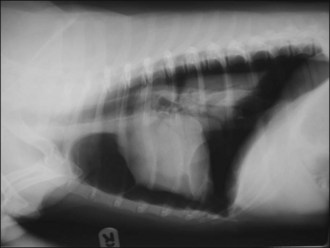

image image

Figure 28.5 (a) Right lateral and (b) dorsoventral thoracic radiographs of a cat showing diaphragmatic rupture.